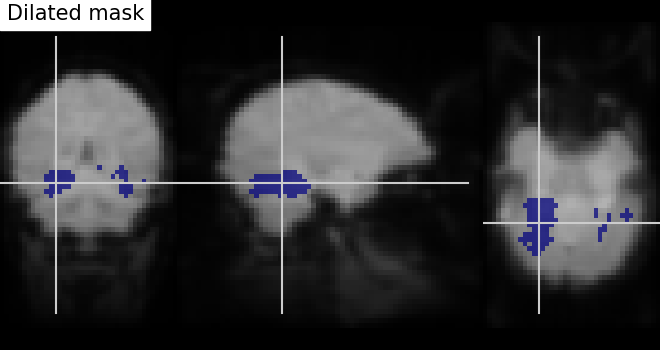

Dilation - Thresholded functional brain images often contain scattered voxels across the brain. To consolidate such brain images towards more compact shapes, we use a morphological dilation. This is a common step to be sure not to forget voxels located on the edge of a ROI. In other words, such operations can fill “holes” in masked voxel representations.

# We use ndimage function from scipy Python library for mask dilation

from scipy.ndimage import binary_dilation

# Input here is a binarized and intersected mask data from previous section

dil_bin_p_values_and_vt = binary_dilation(bin_p_values_and_vt)

# Now, we visualize the same using `plot_roi` with data being converted

# to Nifti image.

# In all new image like, reference image is the same but second argument

# varies with data specific

dil_bin_p_values_and_vt_img = new_img_like(

fmri_img, dil_bin_p_values_and_vt.astype(int)

)

# Visualization goes here without 'L', 'R' annotation and coordinates being the

# same

plot_roi(

dil_bin_p_values_and_vt_img,

mean_img,

title="Dilated mask",

cut_coords=cut_coords,

annotate=False,